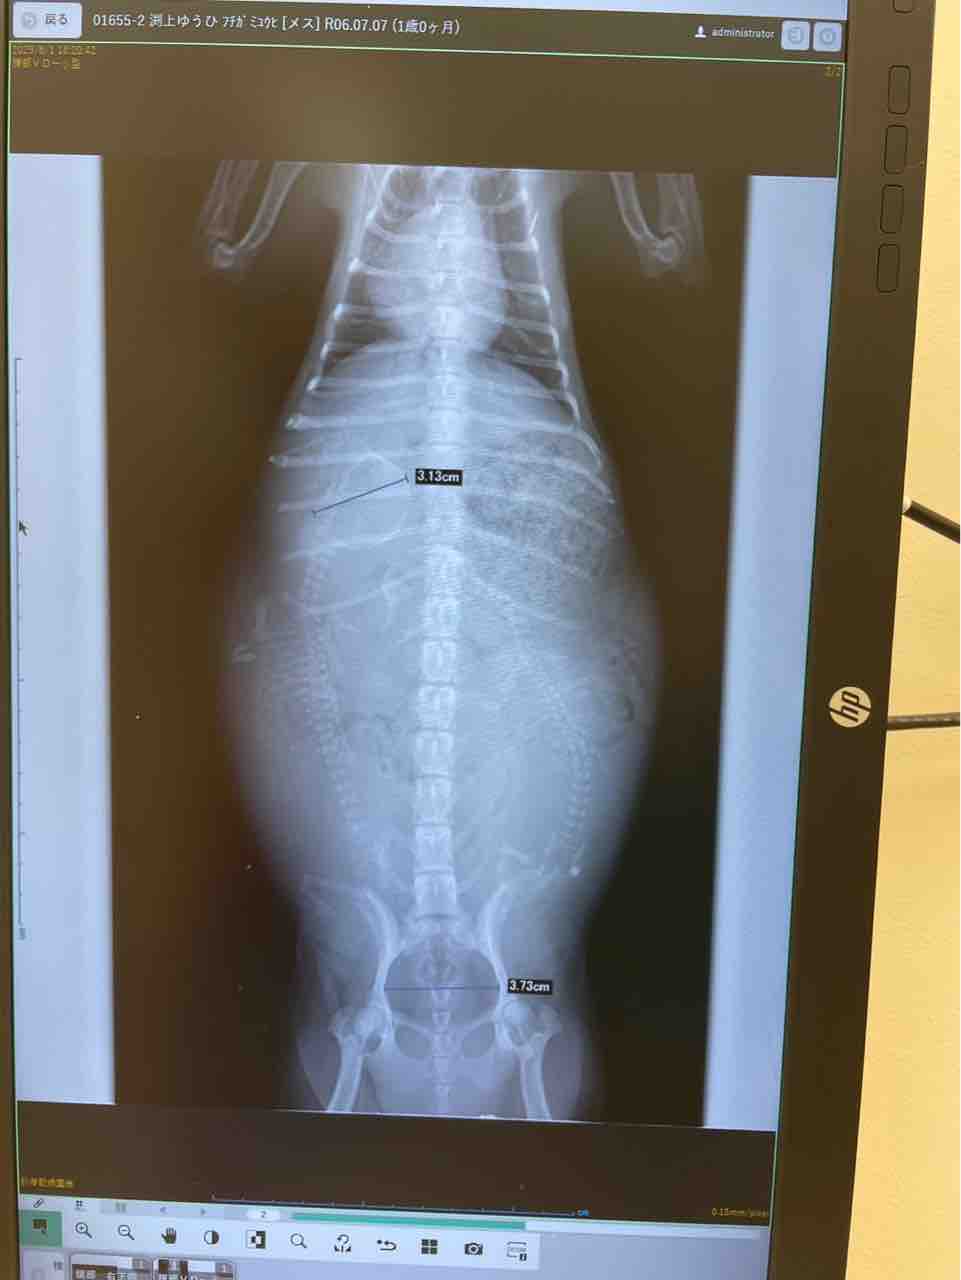

夕陽がお母さんになって、たしかに自分で頑張って産んでくれたふたつの命。

僕が及ばすで、そのふたつの命をどちらも助けてあげることすら出来ませんでしたが、でも確かに夕陽はお母さんとして尽力してくれました。

朝陽を待たずして逆子で早産で生まれてきちゃった朝陽ちゃん。

190g以上の大きさで。もうしっかり育ちすぎてたから早く外に出てきたかったんだよね。

妹の楓は未熟な手足で、模様は晴太そっくりな白黒のマーブル模様。